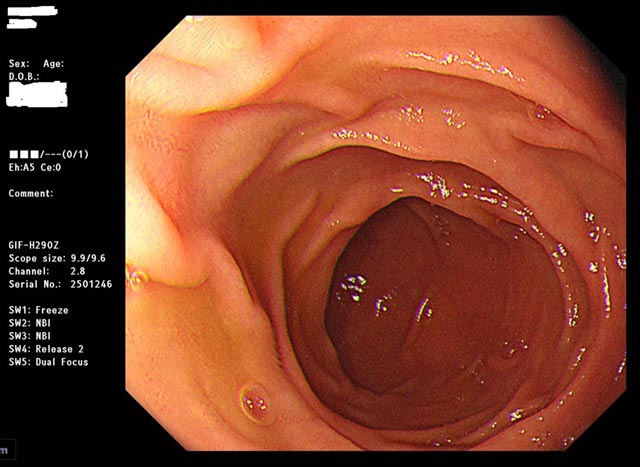

除了癌症判定,經由特殊光譜NBI、BLI以及放大效果,也可協助醫師立即 診斷瘜肉的好壞。簡單來說,就是讓 內視鏡 的訊號經過AI BOX即時處理,就能即時顯示於螢幕上,類似於醫師的第三隻眼睛,幫助揪出不易用肉眼檢視到的瘜肉。